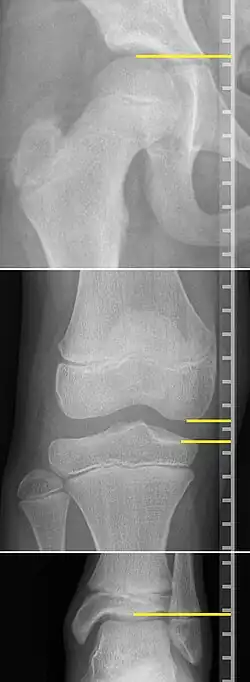

On X-rays, there is generally measurement of both the femur and the tibia, as well as both combined.[4] Various measuring points for these have been suggested, but a functional method is to measure the distances between joint surfaces:[4]

- Femur length: The superior aspect of the femoral head and the distal portion of the medial femoral condyle.

- Tibial length: The medial tibial plateau and the tibial plafond

- Teleroentgenogram, which projects the entirety of both legs at the same time.

- Orthoroentgenogram, which takes separate images of the hip, knee and ankle.

On X-rays, the length of the lower limb can be measured from the proximal end of femoral head to the center of the plafond of the distal tibia.[13]